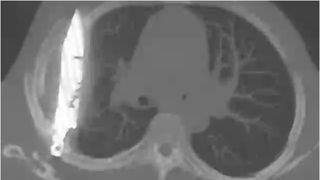

Radiografia a dezvăluit că bărbatul avea un cuțit de dimensiuni considerabile înfipt adânc în piept!

După ce au solicitat o radiografie, a fost găsit un „obiect metalic” imersat, iar medicii și-au dat seama că este o lamă lungă de cuțit, înconjurată de „puroi și țesut necrotic”.

În urma discuțiilor cu pacientul, s-a aflat că acesta fusese înjunghiat în urmă cu 8 ani, iar lama metalică intrase în corp prin umărul drept.